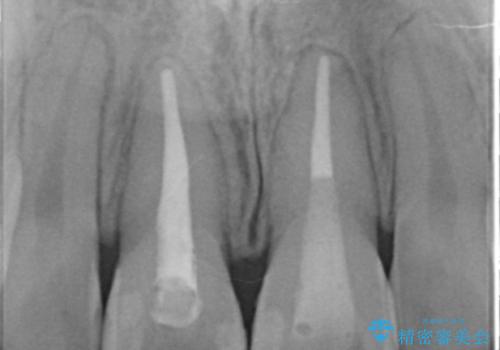

- 神経のない前歯が変色していたため、矯正治療後にセラミックで修復しました。

右の前歯は当院で根管治療をやり直しています。(根管治療はDr.大元が担当しました。)

- 38万円(上顎両側1:ジルコニアクラウン スタンダード 10万円x2、ファイバーコア 2万円x2、 精密根管治療(再治療)9万円x1、仮歯 1万円x2)、ホワイトニング(エクセレント)3万円費用は治療当時の料金となります